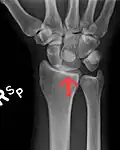

Perilunar dislocation as seen on x-ray.

The lunate bone is the most frequently dislocated carpal bone.